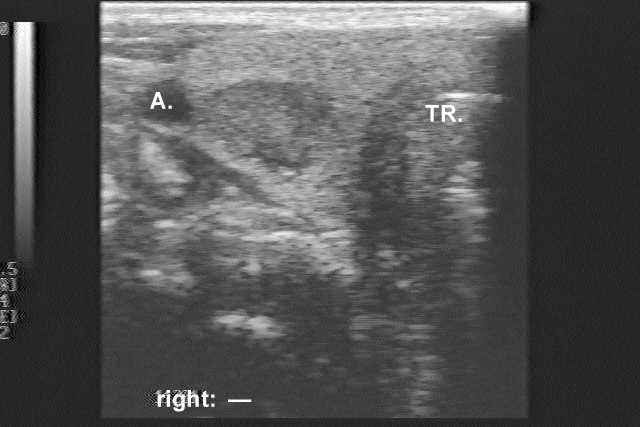

Clinical presentation: A 51-year-old woman was referred for FNAC of a suspected metastasis of a breast cancer to the thyroid. She has been operated for ductal invasive breast cancer on the left 6 months earlier. Ultrasonography of the thyroid revealed a multinodular goiter.

Ultrasonography. There were two hypoechogenic nodules in the right lobe.